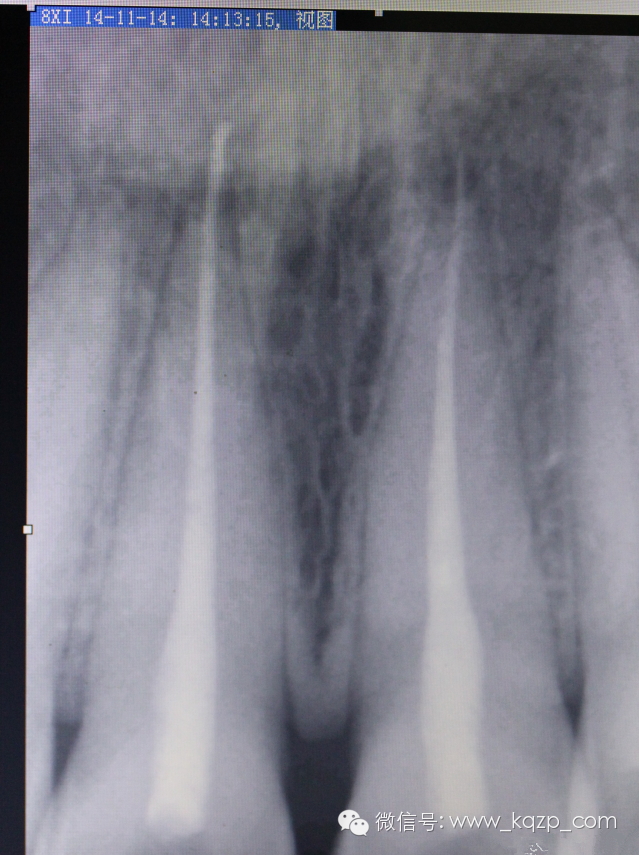

上段牙膠取出無殊,常規(guī)方法。待近根尖時,先用丁克除棉捻軟化片刻不超過5分鐘,拿出棉捻,用拔髓針輕柔緩緩旋入,此時如果有稍緊的感覺即停,試著慢慢拉出,多數(shù)會把根尖部的牙膠完整帶出。

哈哈,成功了。

拍片,

順手把工作長度也確定下。